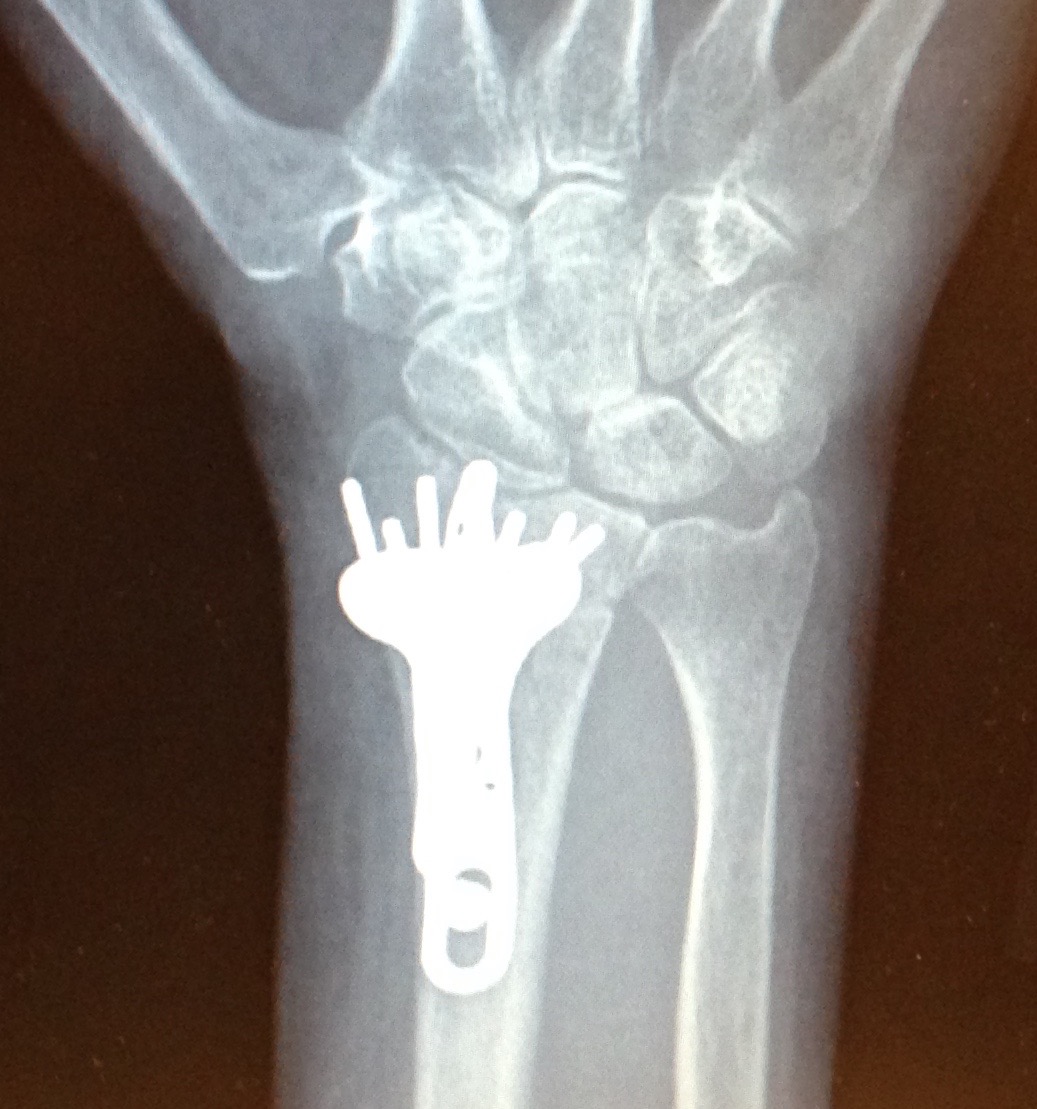

Today is the three-month anniversary of my wrist surgery. I am now the proud owner of two stainless steel plates, thirteen screws, and one big long pin, all holding my wrist in place. I still go to physical therapy every week and do my exercises several times a day. My wrist still hurts but is much better than it was three months ago. I have about half of the range of motion that I had before this break happened. I can use my fingers but do not have much strength in them so gripping anything is difficult. As a result of the surgery, I now also have a trigger finger (the tendon doesn’t glide properly and the finger doesn’t straighten out) and Dupuytren’s Contracture (eventually one or more of my fingers will not be able to straighten out) in my right hand, both of which make getting my grip back a challenge; both things will probably need to be addressed at some future date.